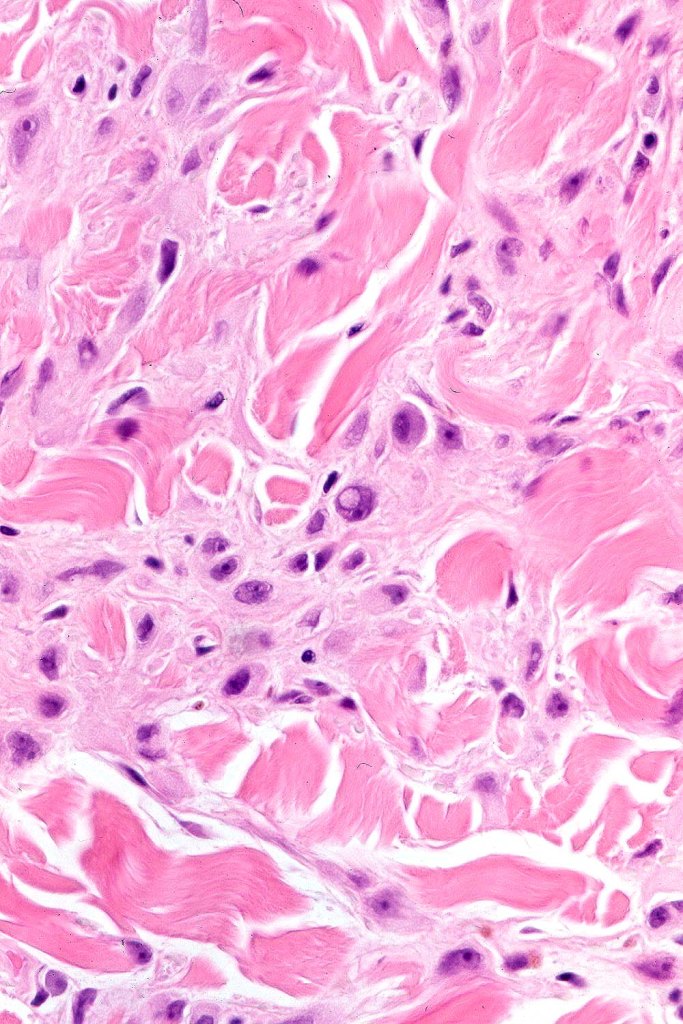

•For the most part, the lesion is composed of somewhat pleomorphic, spindled or epithelioid cells with often abundant eosinophilic cytoplasm & vesicular nuclei with small nucleoli. Melanin is either sparse or absent

•Intranuclear cytoplasmic pseudoinclusions are generally present

•With increasing depth (or age of the lesion), the nevus cells are separated by a dense, sclerotic stroma